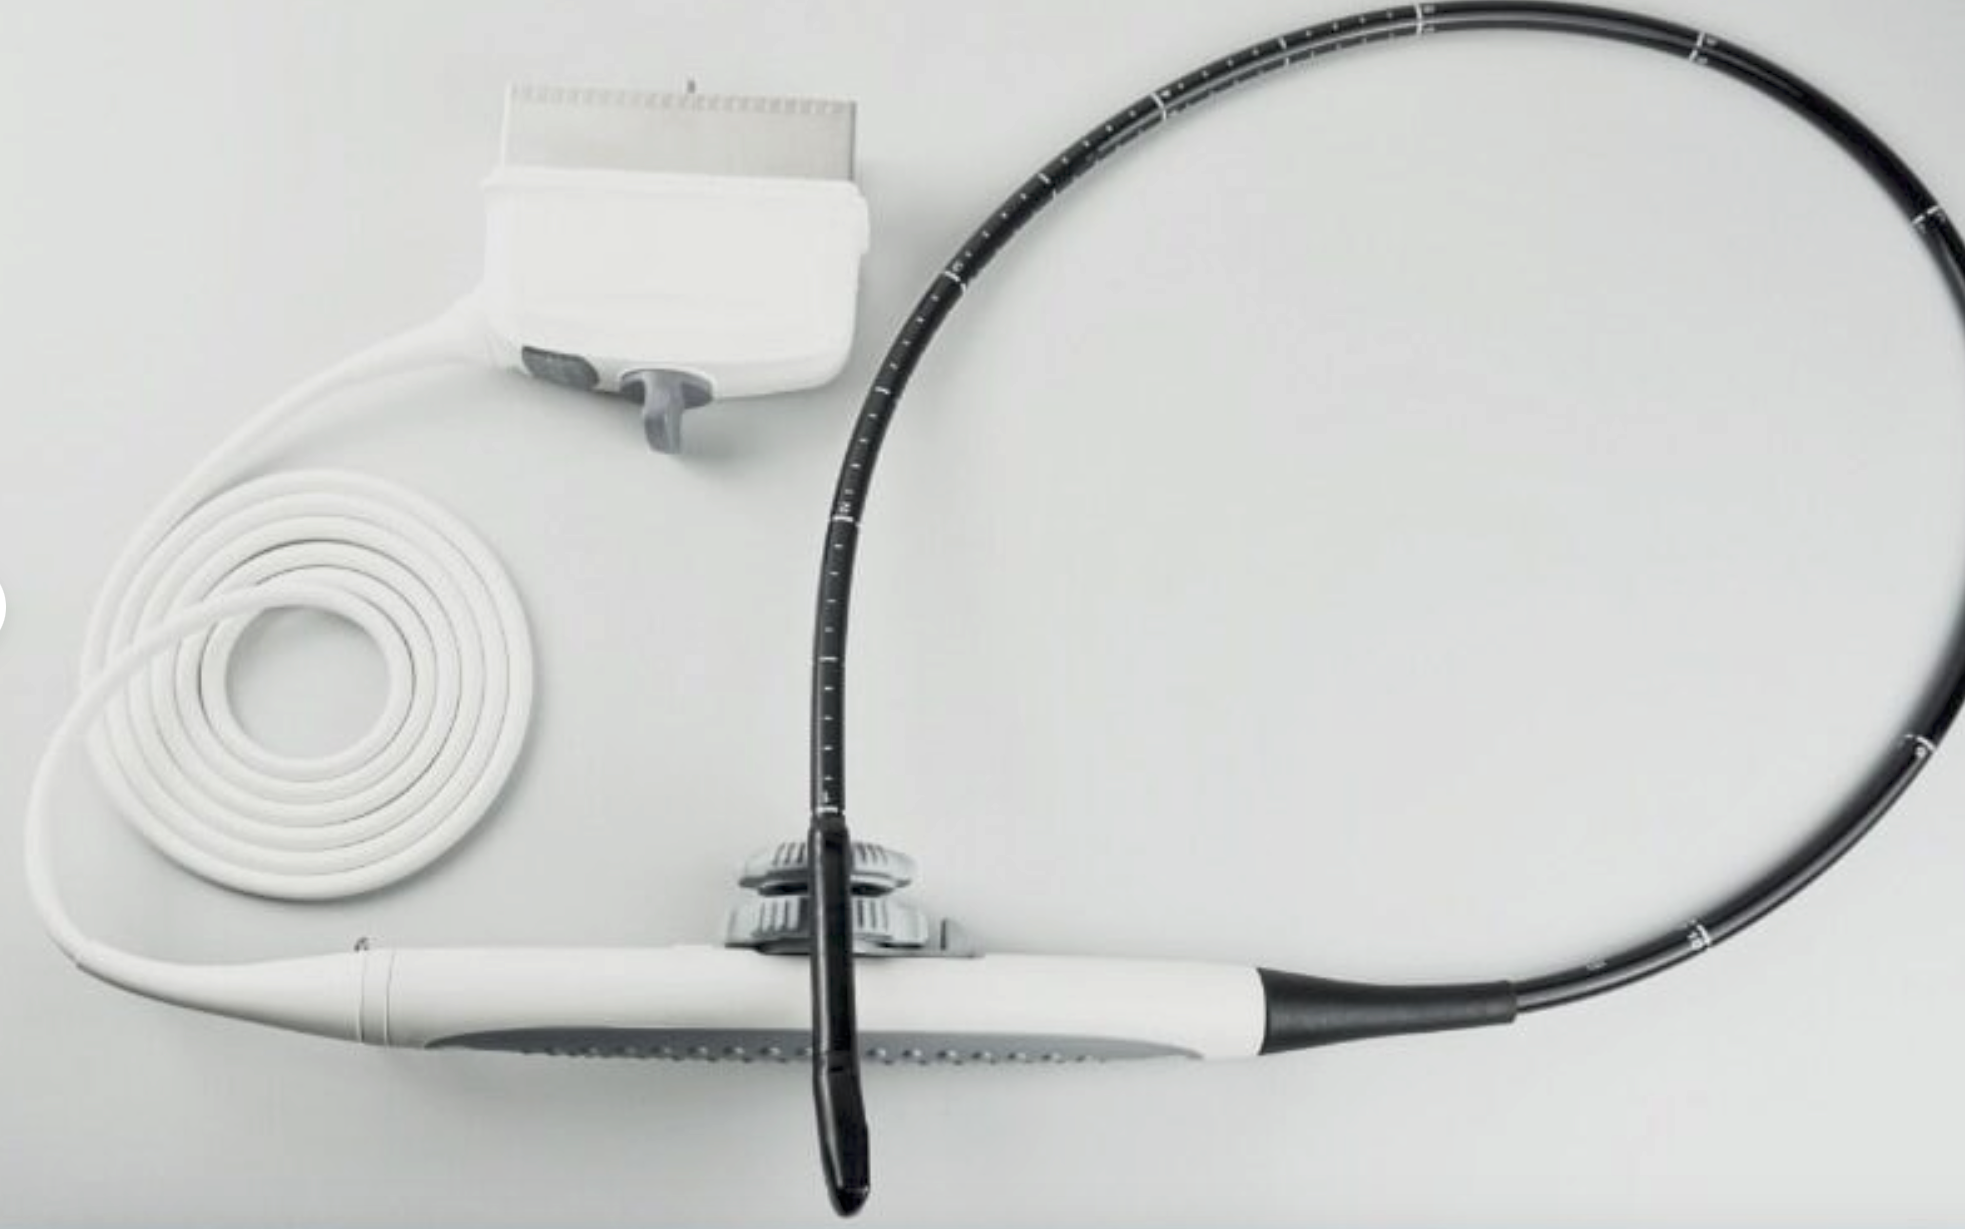

DIAGNOSTIC ULTRASOUND MACHINES FOR SALE

Affordable Color Doppler Ultrasound w/ Convex and TV Probe, PW, Multi Lang.

Sale price$ 1,639.18

Regular price$ 1,999.00